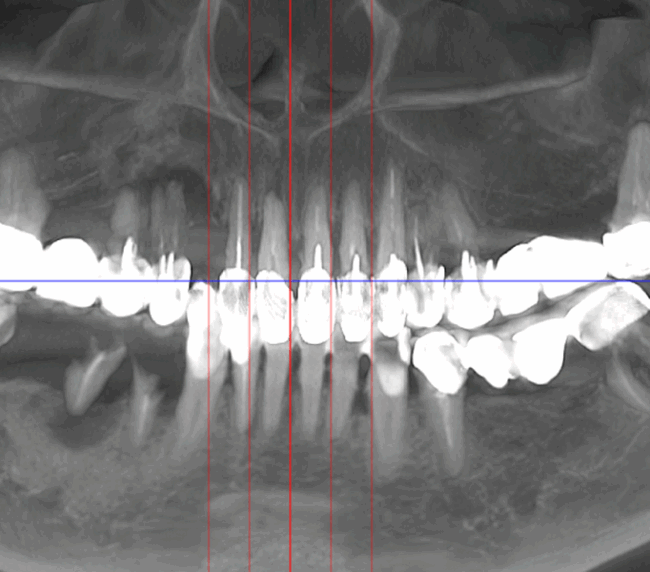

- Investigație imagistică completă, ideal CBCT (computer tomografie);

- Consult clinic detaliat și obiectiv;

- Planificare computerizată a intervenției, inclusiv realizarea și utilizarea ghidului chirurgical, dacă este necesar;